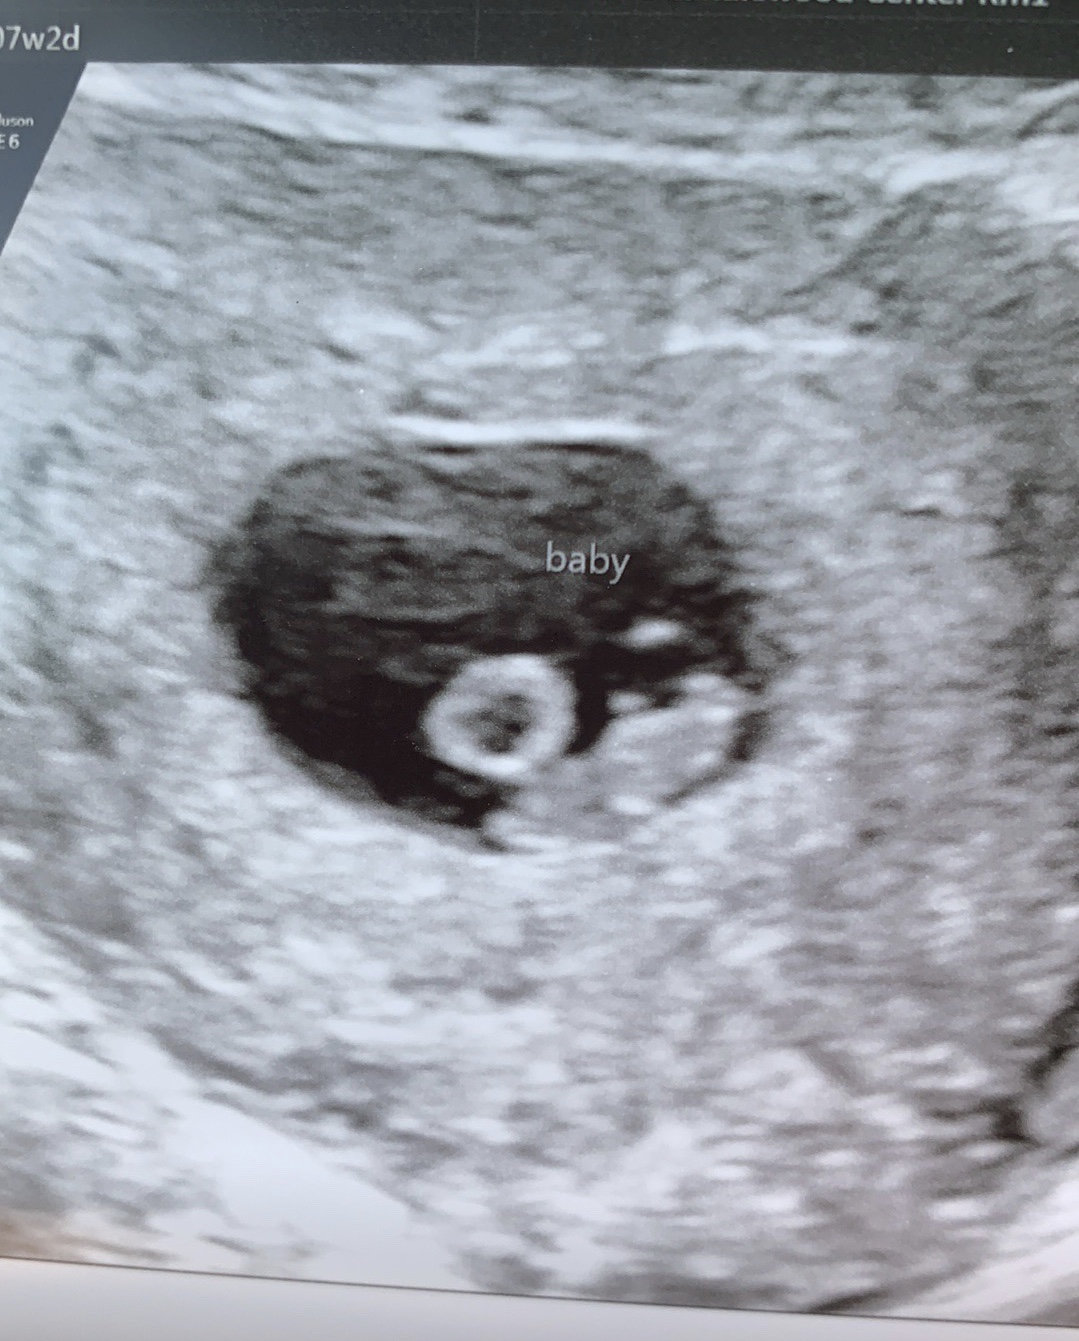

Measuring exactly what we thought it should be (7 weeks 6 days) and heartrate of 157 bpm. Definitely cried some happy tears seeing our little gummy bear. ❤ With my first pregnancy I MCd before we even got an ultrasound, so this was really my first experience seeing a baby on the monitor.